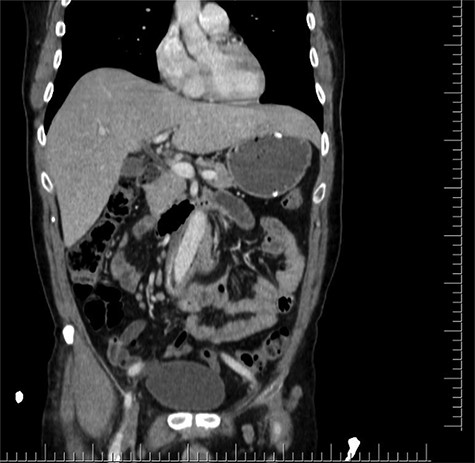

Axial section shows the two limbs of the EVAR, at the bottom. And on top of it, the Dacron straight graft part in the middle of the jejenum.

Distal CT axial section shows the two limbs of the EVAR, at the bottom. And on top of it, the Dacron straight graft part in the middle of the jejenum.

During the first days of December 2018, the patient visited another medical center because of fatigue, difficulty in breathing, lower back pain and inability to walk. His blood biochemistry revealed a very high CRP level (350 mg/dl), and complete blood count revealed a very high level of white blood cells (21 000/ul). An abdominal CT scan illustrated part of the graft was totally eroded into the small intestine (Figs 1–3). The patient was referred to my office and an infectious disease specialist. He had high body temperature (39.5°C) and was lying on the bed with lower extremities adducted to the chest. Antibiotic and supportive treatment was started. Emergency surgery was performed. We found an 8–10 cm of the straight part of the graft had become totally incorporated into the proximal part of the jejenum. The graft was freed, and 10–15 cm of the jejenum was resected and anastomosed. The area was irrigated with saline and hypochlorous acid. We then put a 20 x 10 composite mesh between the vascular graft and the intestine using a non-adhensive surface facing the intestine to prevent future graft and intestine interactions and erosion. After hemostasis, two drains were placed retroperitonally, and the abdomen was closed. On the fourth post-operative day, a high body temperature and high CRP levels were recorded. An abdominal CT revealed retroperitoneal abcess formation. During relaparotomy, the anastomosis was found to be intact, and the retroperitoneal abscess was drained and irrigated with saline. The drains were reinserted. After a month, he once again started to have high fever and high CRP levels. Again, an abdominal CT revealed abscess formation. This time, the abscess was approached transcutaneously. By making an incision in the proximal left lomber region, the abscess was drained. Another incision was made distally, and two drains were placed in the retroperitoneal area.

Coronal CT section shows straight part of the Dacron graft in the jejenum.